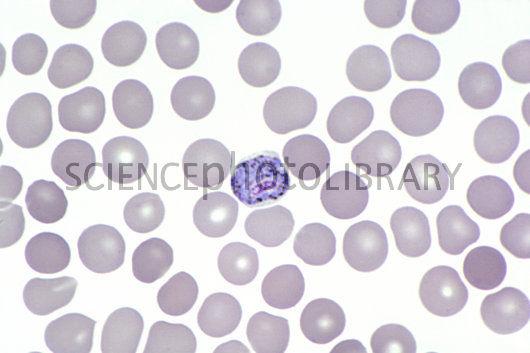

Name the plasmodium species that causes anemia.

Merozoites

Protozoa-plasmodium

Plasmodium falciparium

Vector is anopheles mosquito (female mosquito)

causes more virulant malaria